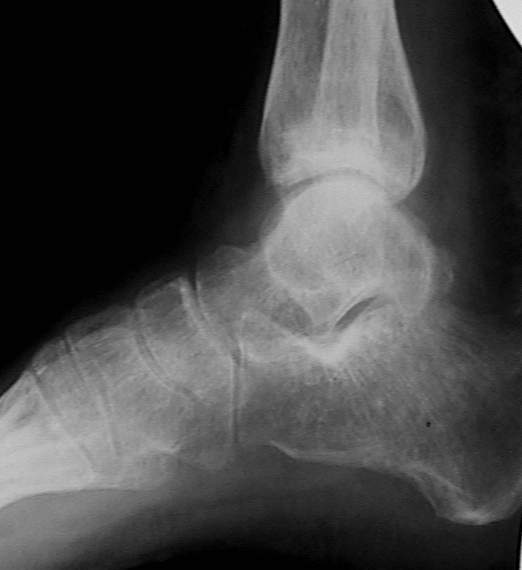

У больного травма в августе 2001 г. Лечился консервативно, Проводилась иммобилизация гипсовой лонгетой 3 мес. В последующем местное лечение. Остается контрактура боли в области наружной лодыжки. Направлен в наше отделение в конце января 2002 г Планируется костная аутопластика, остеосинтез пластиной, винтами перелома наружной лодыжки. Решается вопрос о коррекции неправильно сросшегося перелома внутренней лодыжки. Рентгенограммы: фас; профиль; план Сергей Зырянов

на снимке, кстати, срезан ее дистальный отдел, и правильность взаимоотношений с таранной костью не оценить. Если они правильные - я бы присоединился к мнению об оставлении ее покое.

А вот укорочение внутренней, похоже, привело к натяжению дельтовидной связки и гиперпрессии в медиальном отделе сустава, и уже сейчас там

видно сужение щели. Так что есть смысл обратить внимание на ортопедическую профилактику деформирующего артроза.

Надо сделать компьютерную томография и объектизировать истинное состояние переломов лодыжек. Пока не видно подвывиха таранной кости, а ложный сустав внутренней лодыжки (я его не вижу)в основном не вызывает функциональных растройств в голеностопном суставе.

Коллеги! Я думаю надо плясать от возраста, профессии, объёма движений и интенсивности болевого синдрома. Ничего подобного не прозвучало... Имеет место подвывих стопы кнутри, никем не отмеченный! Оно конечно варус лучше, чем вальгус, но в данном случае принципиально его устранение (если оперировать конечно). Если оперировать, то предлагаю: